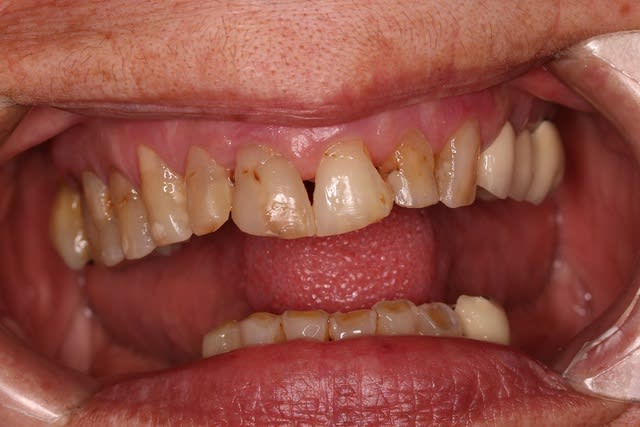

Bon pour le haut ça va être traitement CCAM à base de couronnes.

Le bas, on garde ou on vire ? 34 mobile, le reste ça bouge pas.

Jusqu'à la photo 3 j’étais pour le traitement CCAM (disque diamanté+foret + empreinte.... nan je déconne pas le disque... humm ...nan).

Au vu de la photo 4 le plan de traitement est purement verbal:

"Votre cas est trop complexe pour moi, allez à la ville ya plein de cador moi je fait que les cas facile." Vu qu'il portera peut-e^tre pas son stéllite ( CCAM toujours) j'aurais trop peur pour mes cerams.

sinon pour le bas je vire pas si le patient en fait pas la demande ou ne signe pas pour au moins des locator.

Ce sont des érosions chimiques en palatin, je pense :)

Oui , aller,,on garde le bas qui nous servira de repère pour faire le haut

Chimique ? Je dirais non

Pourtant tu as bien un bandeau d'émail périphérique résiduel typique d'une érosion, non ?

(je parle du bloc antérieur supérieur, en palatin)

Je garderai tout ce qui ne bouge pas en bas. Virer des dents immobiles et asymptomatiques c'est sévère ! ;) Un bon bloc d'ancrage pour le stellite.

Pour moi l'usure en haut est purement mécanique.

ah ben non pas chimique non plus , la mamie , elle grignote avec les quenottes de devant , tel un petit lapin ! parce qu'elle a plus rien derrière ... faut pas lui enlever ses dents ....et refaire en sorte qu'elle se serve des molaires ... j'ai bon là Enlaye ?

Pour le haut, je reste sur mon idée d'érosion, même si ça change les paramètres de collage, on s'en fout un peu au final.

Heuuu , t'as des dents usées pile poil en face de dents naturelles, elles mêmes usées et tu nous parles d'érosion chimique avec preuve l'appui ? faut sortir la tête des bouquins et ouvrir un peu les yeux ! Et t'as intérêt d'en tenir compte à mon avis ...Maintenant qu'elle sirote du jus de citron pourquoi pas mais la cause principale est mécanique !

alors , il peut effectivement y avoir une cause chimique , mais pas celle que l'on croit :-)))

je penserais à des antidépresseurs .

ils augmenteraient l'asialie ,du coup ,les dents s'useraient a grande vitesse par manque de lubrification .ce qui pourrait aussi expliquer l'etat du haut et des gencives ......